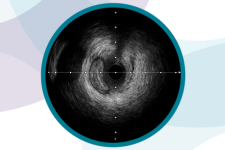

血管内超音波イメージングカテーテル

![]() |

OPTICROSS™ HD Plus |